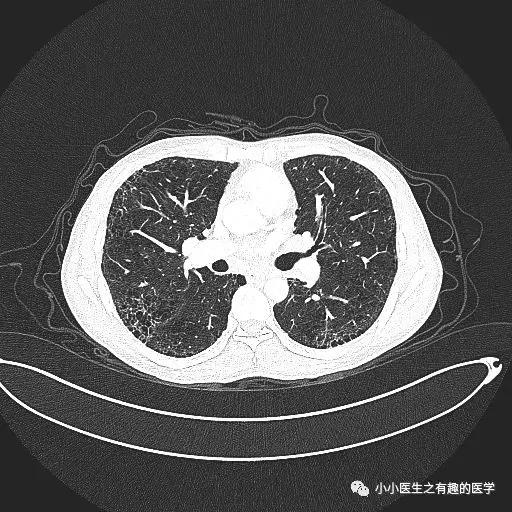

间质性肺炎的影像学表现,复杂的很复杂,有时候和肺炎不容易区分。

经典的间质性肺炎,就是一张网!

1.胸膜下2.网格状很多间质性肺炎,都有这个特征,是间质性肺炎的入门知识,也是很重要的知识。